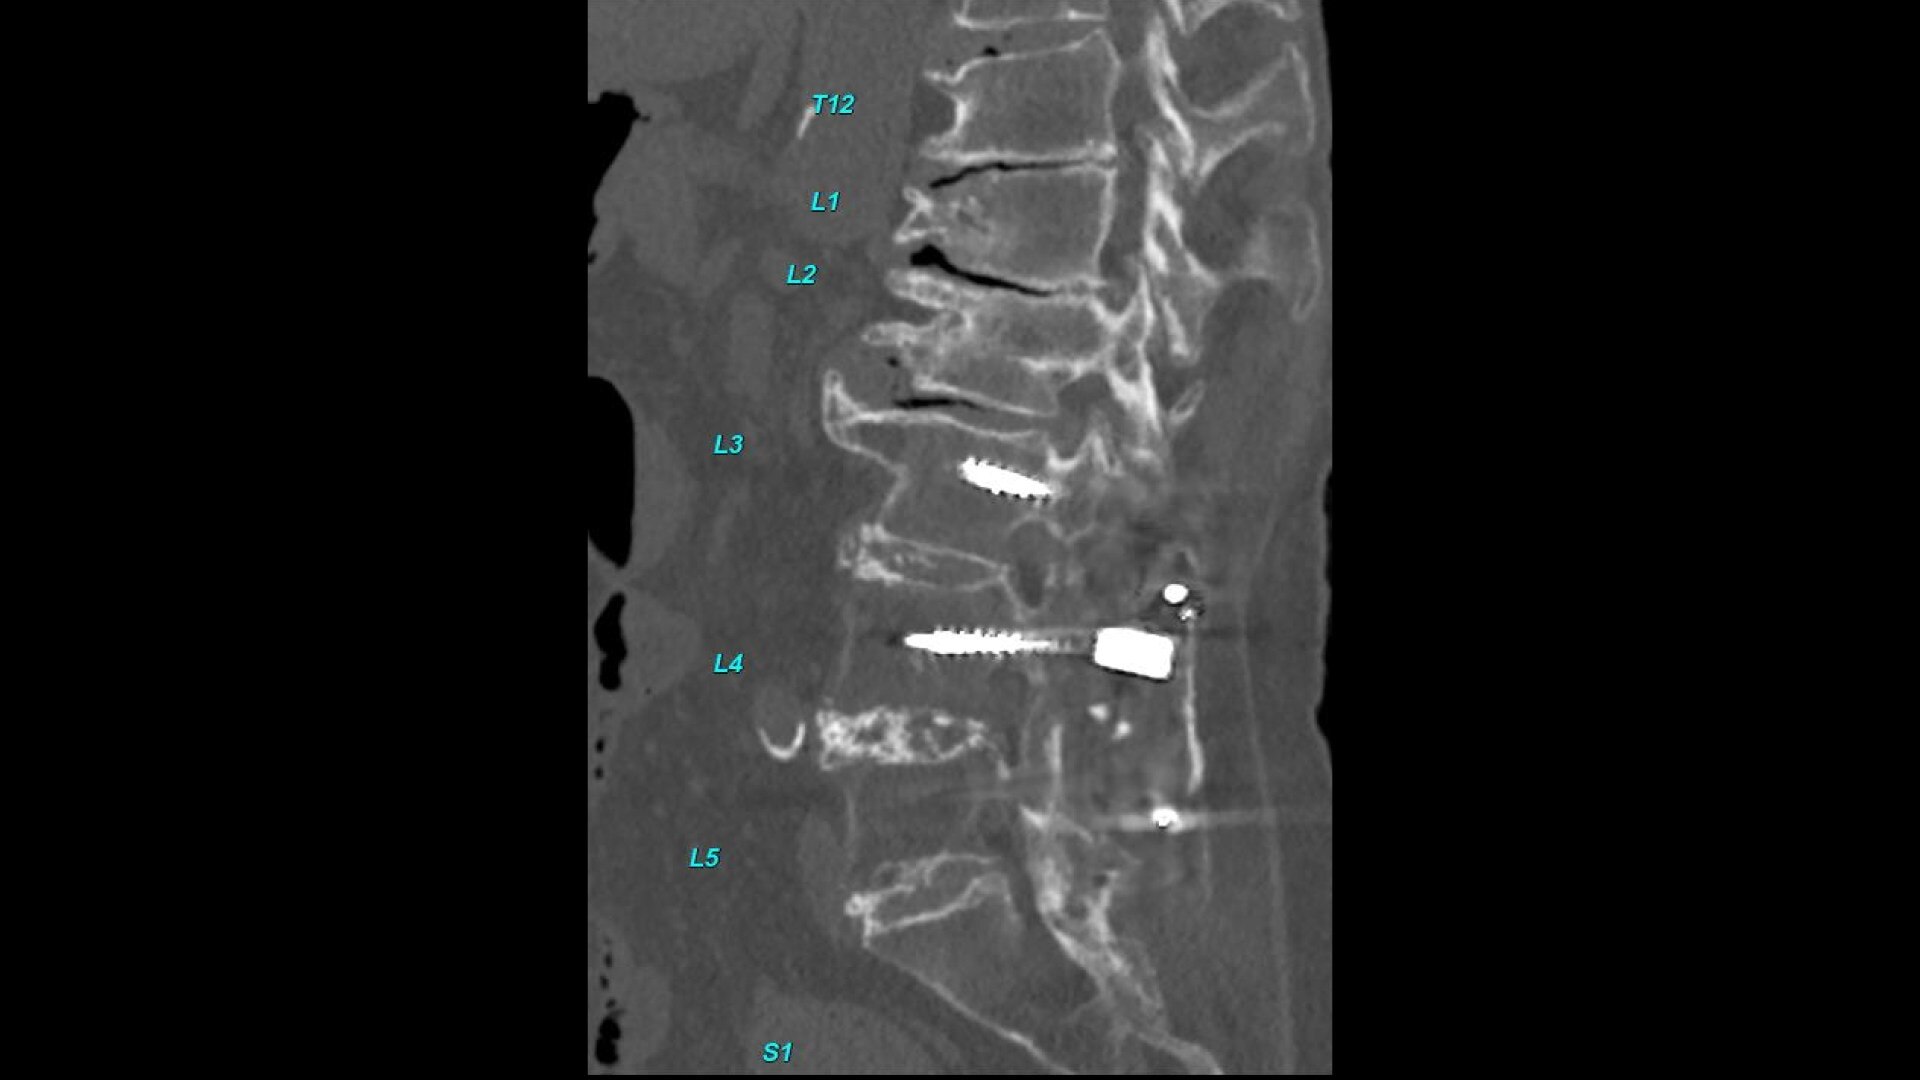

Bone VCAR

Spine assessment with deep-learning based CT application.

• Automated generation of a 3D trace to generate oblique and straightened reformat views

• Automated generation of oblique views perpendicular to vertebral bodies and disc spaces

• Accessible for any exam type: trauma, oncology, dedicated spine, general imaging

• Load multiple series and vertebrae labeling will propagate to the different volumes